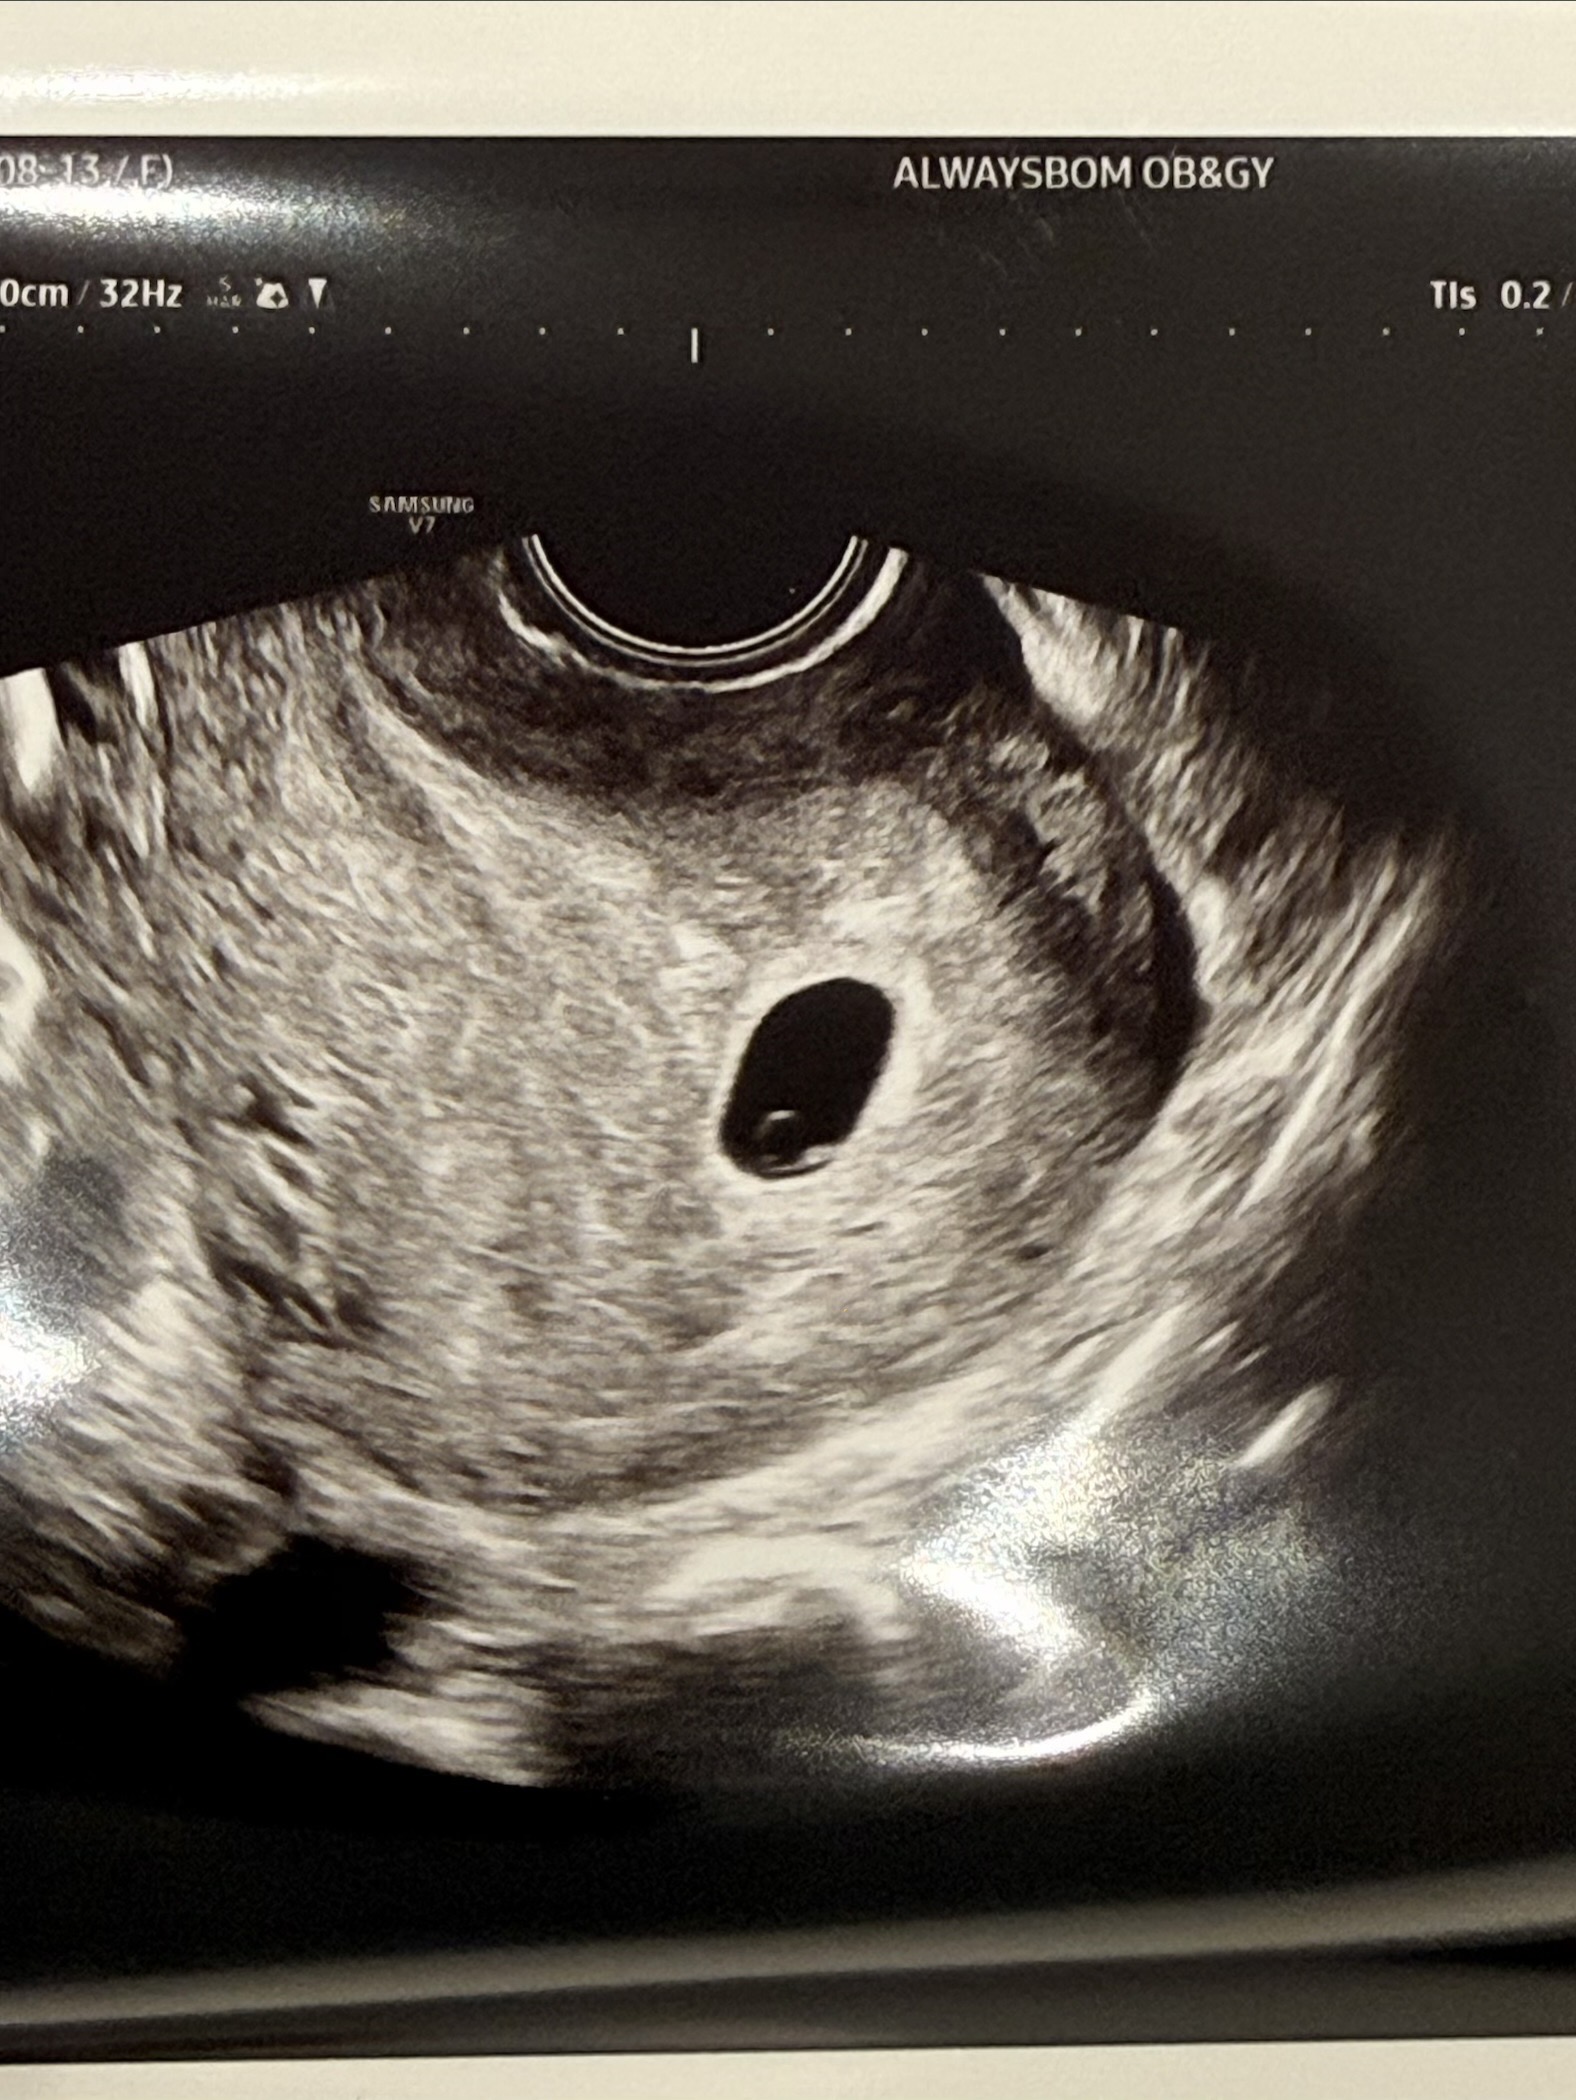

5주 3일 다이아반지 보고 왔어요 💍

막생 기준은 6주지만! 아기집 크기로 지난주에 4주 3일, 오늘 5주 3일이네요 ㅎㅎ 7월에 유산을 한 번 했어서 걱정했는데, 걱정이 무색하게 예쁜 다이아반지 들고와줬어요 🥹 (이번에 다이아 너무 보고싶어서 저도 다이아반지 끼고 간건 안비밀 (?)) 다다음주에 심장소리 들을 수 있다는데, 다음주 월요일 분만병원 진료거든요! 그때 더 일찍 봤으면 좋겠다는 생각도 드네요 ㅎㅎㅎㅎ 베동 분들도 기다리시는 만큼 아가들이 프로포즈하러 얼른 달려가길 바라는 마음입니다 🤍